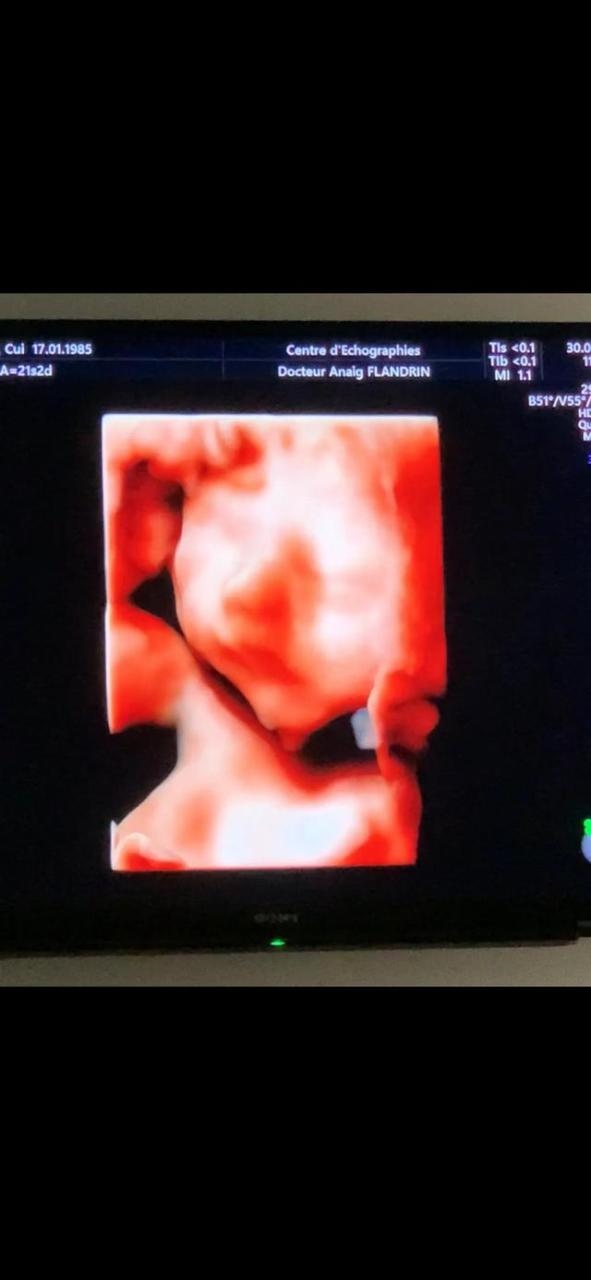

下面是我男宝宝的照片,不爱笑 可能和我脾气不好有原因吧,脾气在调理中。怀孕了还要照顾大宝 照顾家务 实在力不从心。这次怀孕特别累但是也很期待他的出生。预产期是十一月初。